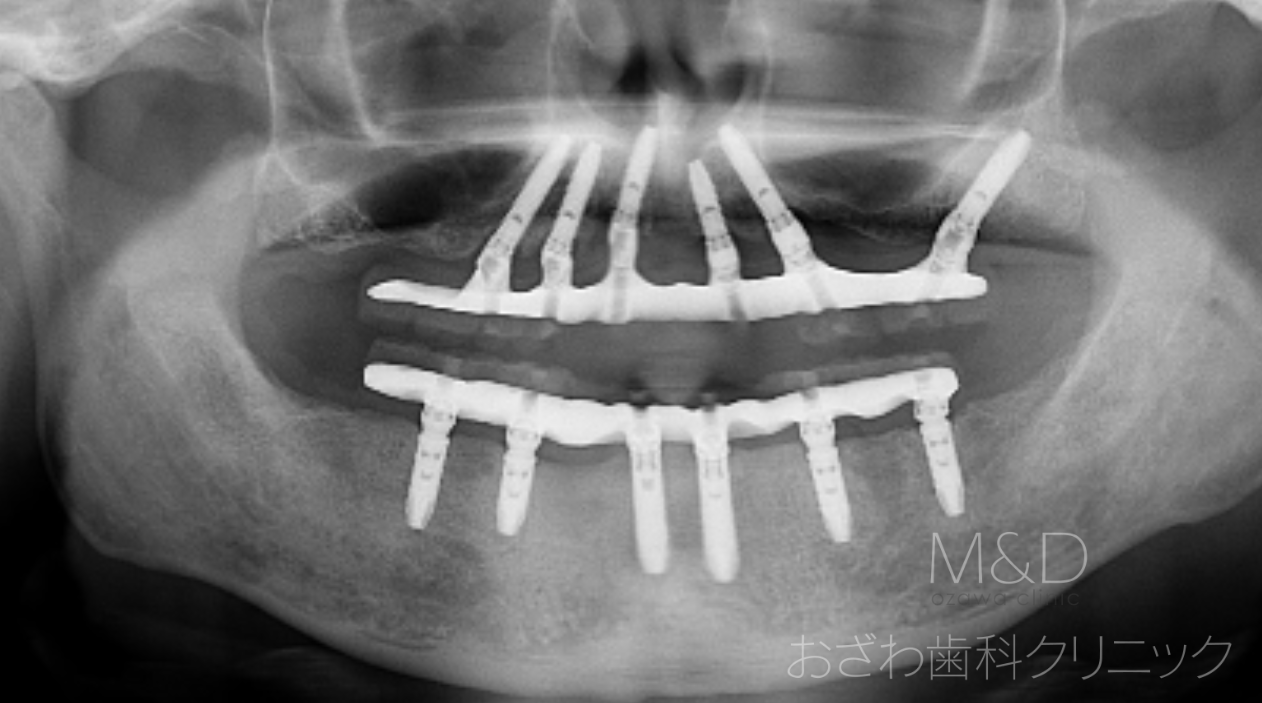

術後

上下顎残存歯の抜歯、上顎6本、下顎6本インプラント

上下顎共(即時負荷:オペの日に仮歯が入ります)